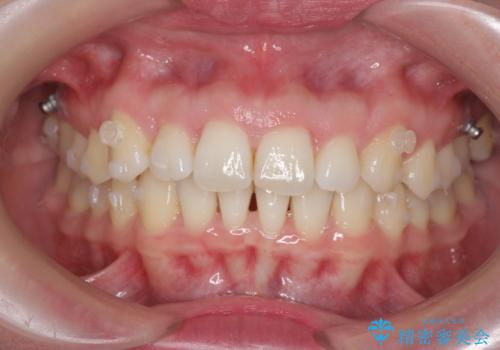

- 前歯の突出感、出っ歯の治療を希望され来院されました。

インビザラインを用いた治療計画を立て、しっかりと出っ歯を治すためにマイクロインプラントを併用します。

マイクロインプラントを併用することでしっかりとマウスピース全体を後方へ引き、前歯の突出感を改善することができました。